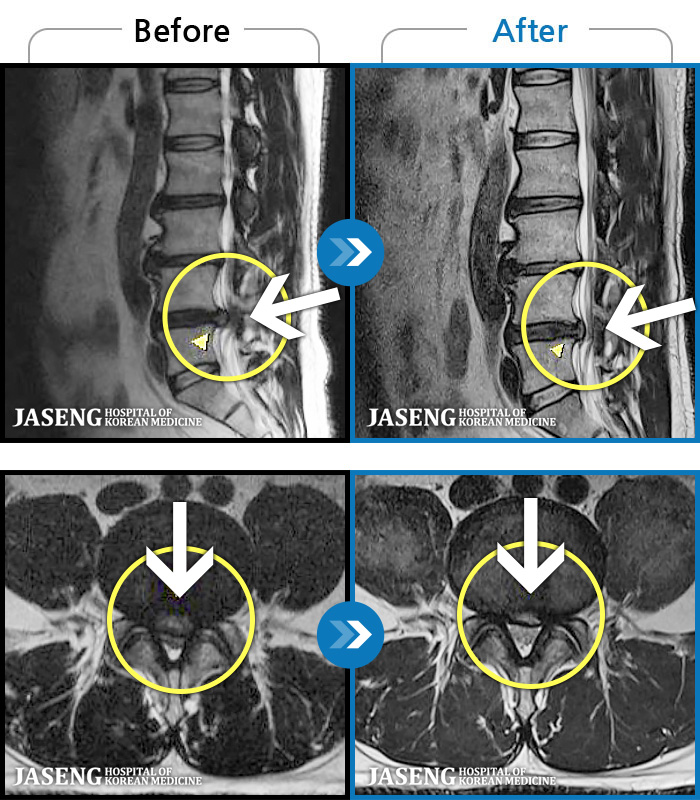

94 MRI ũ ʸ Ȯϼ.

[] 03.04.01~09.11.01